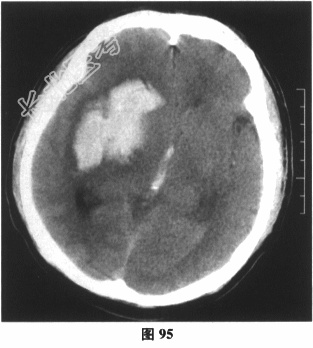

患者男性,50岁。主诉:言语不利、左侧肢体无力3小时。现病史:患者3小时前与家人发生争执后出现言语不利、流涎,同时出现左侧肢体无力,不能行走,头部持续胀痛,遍及整个头部,频繁呕吐,喷射性,为咖啡色胃内容物。家人急送当地医院急诊,神经系统检查:神志清楚,构音不清,双侧瞳孔等大等圆,对光反应灵敏,各方向运动充分,左侧鼻唇沟浅,伸舌左偏。左侧上肢肌力2级,左下肢肌力0级,左侧Babinski征(+),颈无抵抗。既往史:高血压病史10余年,平素不规律服用降压药物。

当地医院急诊测血压为220/130mmHg,查颅脑CT(图95)。